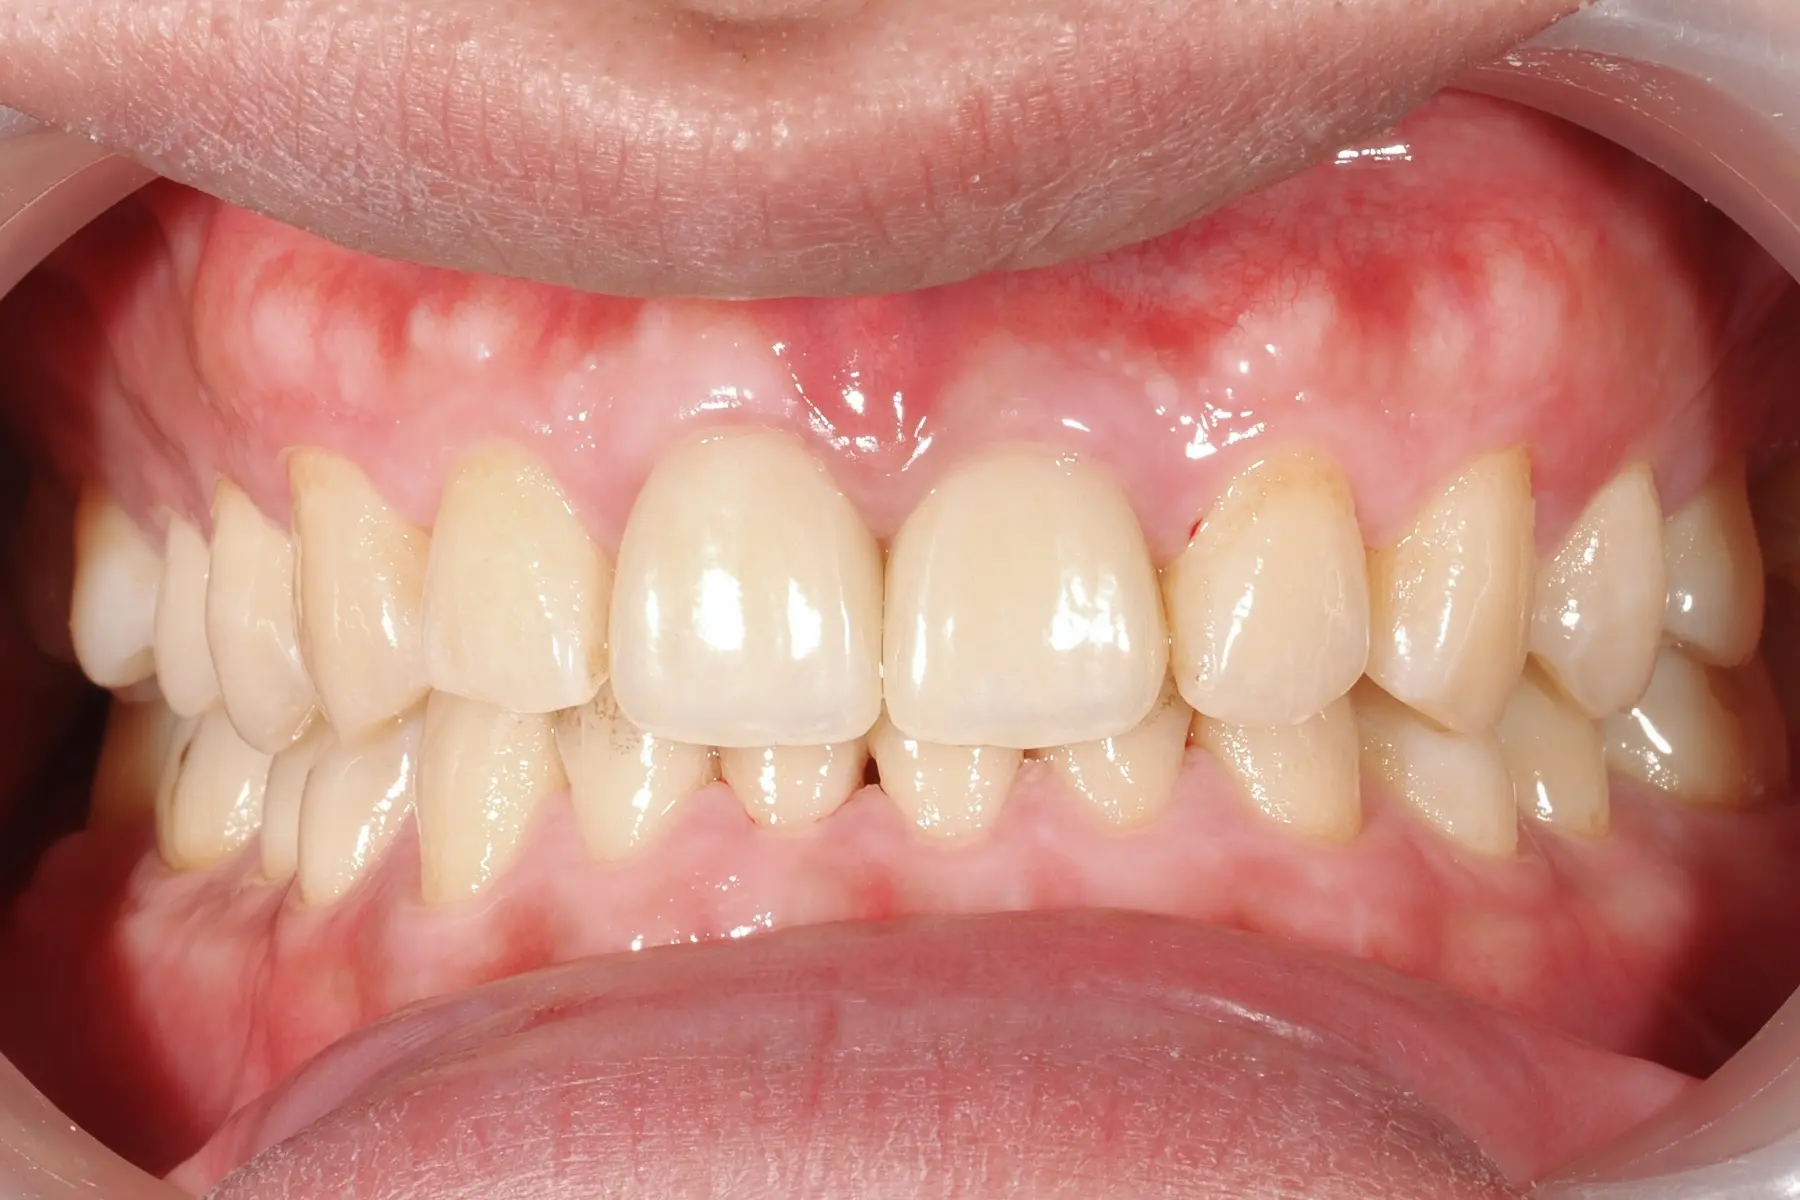

• 術前 42

術後 40

牙周治療

主治醫師

• 鍾國耀

治療時間

三次療程

主訴

牙齦紅腫出血、牙縫容易塞食物